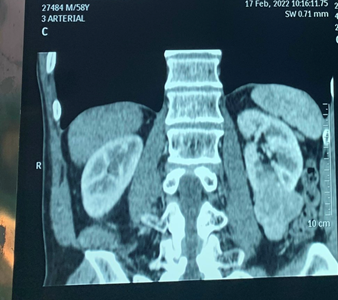

Hình ảnh khối u qua CT Scan

Ung thư tế bào thận là ung thư thường gặp của niệu khoa. Điều trị tiểu chuẩn cho ung thư tế bào thận là phẫu thuật cắt thận mà trong đó phẫu thuật cắt thận nội soi sau phúc mạc là phương pháp phẫu thuật mang lại nhiều kết quả tích cực như bệnh nhân hồi phục nhanh, ít đau sau mổ,... Vừa qua, Bệnh viện Trường Đại học Y Dược Cần Thơ vừa tiếp nhận và điều trị thành công cho bệnh nhân nam T.D.T 58 tuổi với chẩn đoán là u thận trái. Bệnh nhân vào viện với các triệu chứng đau âm ỉ hông lưng trái, tiểu máu.

- Thông thường, u thận có thể được chẩn đoán thông qua việc chụp cắt lớp vi tính bụng có tiêm thuốc cản quang. Một khối u thận ngấm thuốc cản quang mạnh gợi ý ung thư tế bào thận